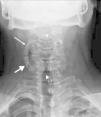

The plain neck X-ray (Fig. 1) performed on admission showed a proximal cervical rib originating in vertebral body C3 in a caudal direction and articulating with another distal supernumerary rib, originating and ascending from vertebral body C7.

DiscussionCervical ribs are prolongations of the transverse process of the seventh cervical vertebra beyond the transverse process of the first thoracic rib. Their incidence is different in different countries,1–7 although it is estimated at around between .2% and 8%, and is more common in women.3,5,7 They can be unilateral or bilateral (the latter comprise 50%–80%), with poor right predominance when they are unilateral.2,8 In 90% of cases they tend to be asymptomatic3,6–8 and are usually diagnosed accidentally when a plain X-ray of the chest or cervical spine is performed for a different reason. Treatment is usually conservative with rehabilitation, except when symptoms occur caused by nerve (brachial plexus) or vascular (subclavian artery) compression,5–7 when the surgical option is taken.4